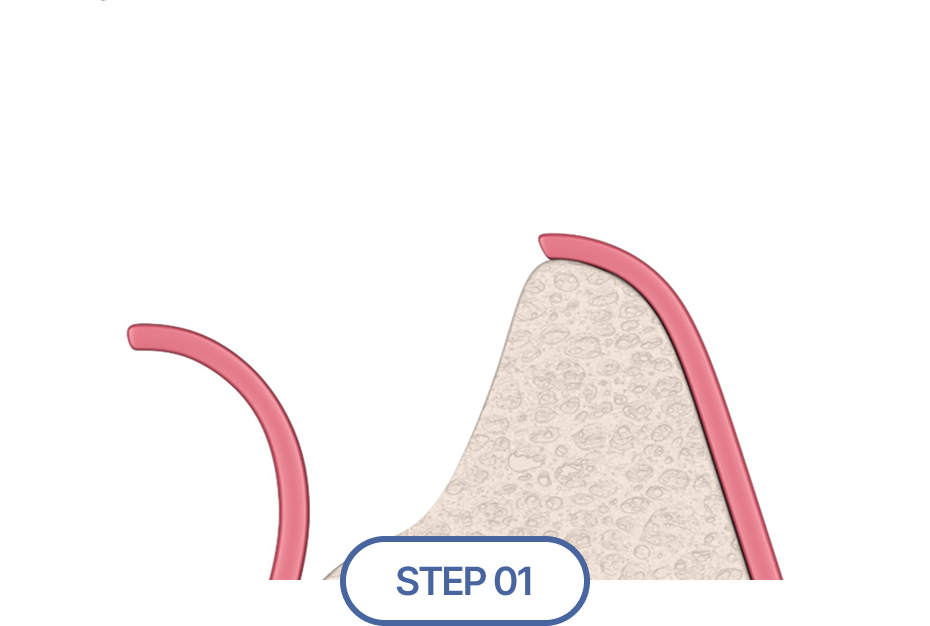

잇몸 뼈 소실 정도 진단

잇몸뼈의 양이 부족해 임플란트 식립이 어렵다면?

뼈이식 임플란트

성공적인 임플란트 식립을 위해서는 충분한 양과 질의 잇몸뼈가 필수적이지만,

경우에 따라 잇몸뼈가 부족한 경우가 있습니다.